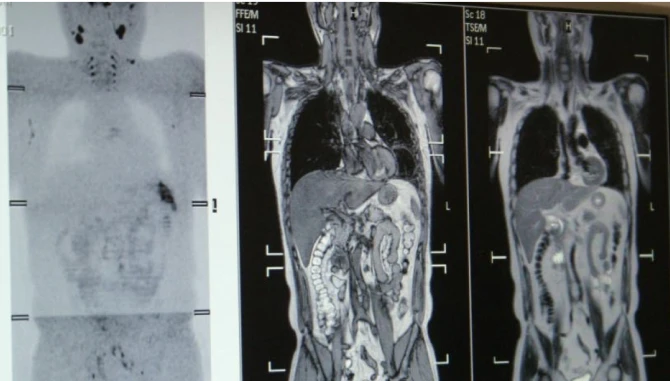

- DWIBS法(全身のがんの分布を明らかにする画期的な方法)

DWIBS法により、従来FDG-PETでしかできなかった全身のがん分布の評価が、MRIで可能になりました。その後、オランダでの研究活動では、世界初となる全身の末梢神経描出にも成功しました。この成果は、医学界で最高峰とされる『ニューイングランド・ジャーナル・オブ・メディシン』にも掲載されています。